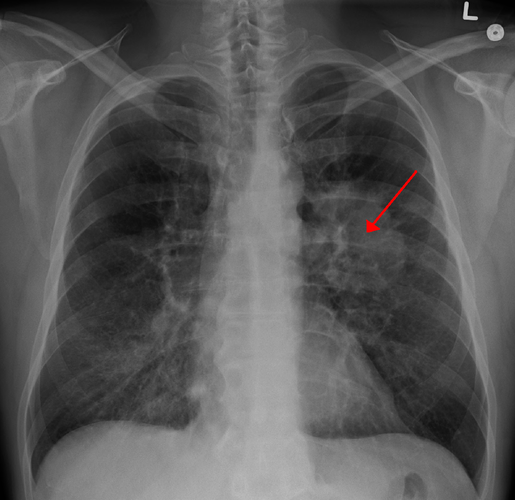

Chẳng hạn, gần đây, một bệnh nhân nhập viện điều trị ngoại trú do lên cơn đau đầu và tưởng là tai biến mạch máu não. (Ảnh: acc.vn)

Qua thăm khám, bác sĩ phát hiện một khối u di căn nội sọ, và khi kiểm tra kỹ hơn thì phát hiện khối u nguyên phát nằm ở phổi. Ảnh: Boldsky.